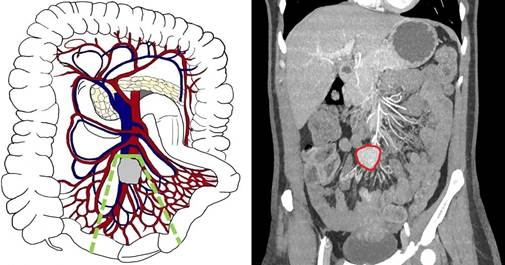

Третий А тип (уровень III по Ohrvall) - распространение опухолевого конгломерата вдоль ВБА и ВБВ, на уровне или ниже a. Ileocolica (рис. 3). Погранично-резектабельный. В данном случае возможно выделение и перевязка вовлеченных радиальных ветвей первого порядка. В подобных случаях, как правило, возникает необходимость выполнять обширные резекции тонкой кишки. Необходимо четко оценить планируемый и возможный объем операции, длину резецируемой и остающейся тонкой кишки и возможность развития синдрома короткой кишки после операции.

Рис. 3. Третий А тип (уровень III) - локализация брыжеечных метастазов на уровне или дистальнее отхождения a. et v. ileocolica, без вовлечения ствола ВБА/ВБВ